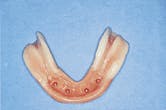

Figure 15-The tissue surface of the mandibular denture that shows the soft liner and the free-end saddle reline impression. I believe that all free-end saddle partial dentures should be relined upon delivery. An implant-retained mandibular denture is a free-end saddle partial.

Figure 15